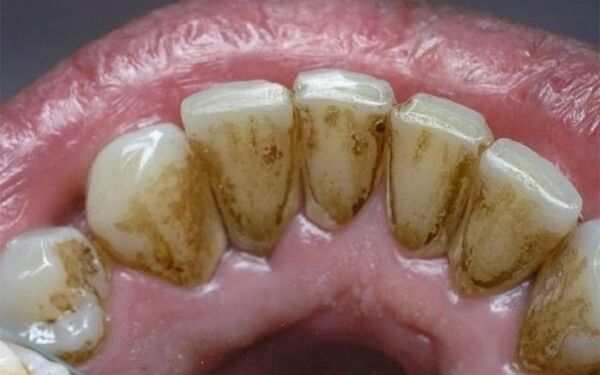

Vôi răng (cao răng) là lớp mảng bám cứng, hình thành từ thức ăn thừa, vi khuẩn và khoáng chất trong nước bọt. Nếu không được loại bỏ bằng cách đánh răng thường xuyên và đúng cách, mảng bám sẽ khoáng hóa thành vôi răng bám chắc vào thân răng và dưới nướu.

Vôi răng không thể làm sạch bằng bàn chải thông thường, mà cần đến nha sĩ để loại bỏ bằng máy cạo vôi chuyên dụng.

Gây mất thẩm mỹ (vôi răng vàng, nâu, đen…)